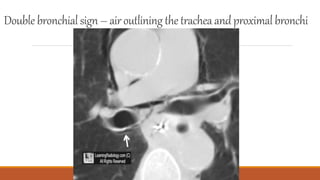

Double bronchialsign – airoutlining thetracheaandproximalbronchi

Double bronchialsign –airoutlining thetracheaandproximalbronchi